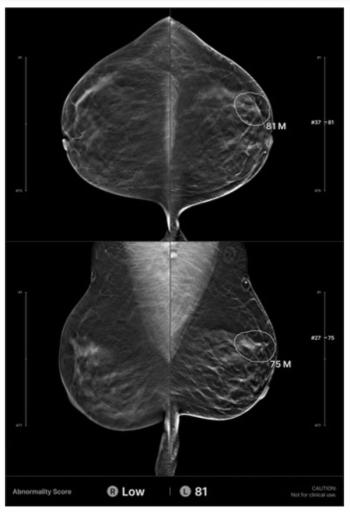

Over 26 percent of AI-detected future breast cancers and interval breast cancers missed by radiologists were invasive cancers, according to newly published research involving over 42,000 women who had 2D screening mammography.

In a retrospective review of screening digital breast tomosynthesis (DBT) exams for over 200 women with interval breast cancers, researchers found that AI provided accurate localization of cancers in 32.6 percent of the cases.